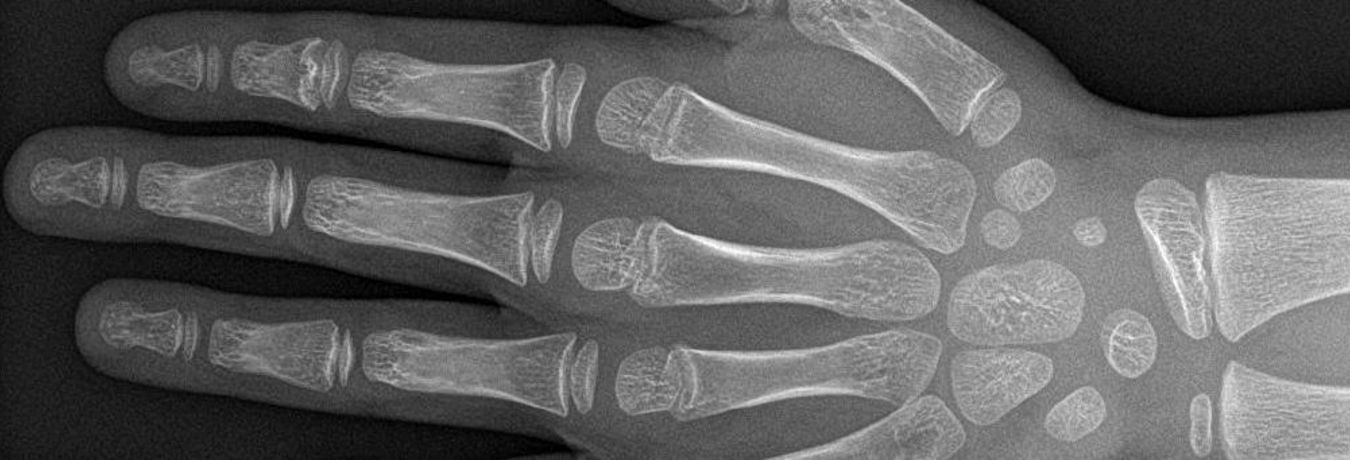

Kinder sind keine kleinen Erwachsenen. Dieser Leitspruch gilt im besonderen Maß für die Diagnostik und Behandlung von Erkrankungen im Kindes- und Jugendlichenalter. Die Kinderradiologie umfasst sämtliche bildgestützte Untersuchungensarten -vom Ultraschall über das Röntgen bis hin zur CT und MRT- vom Frühgeborenen bis zum Erwachsenen.

Kinderkrankheiten erfordern sowohl ein sehr spezielles Wissen, wie auch eine spezielle technische Ausstattung, um schnell und umfassend zu verstehen, was Ursache der Krankheitssymptome ist. Der Strahlenschutz ist hierbei von entscheidender Bedeutung.

In den letzten beiden Jahren wurden sowohl die Röntgengeräte wie das CT-Gerät erneuert. Dies ermöglicht eine optimale Bildqualität bei geringstmöglicher Strahlendosis. Das MRT ist mit spezieller Hard- wie Software ausgestattet, in der Zusammenarbeit mit dem Team der Anästhesie können auch kleinste Kinder schonend im MRT untersucht werden.